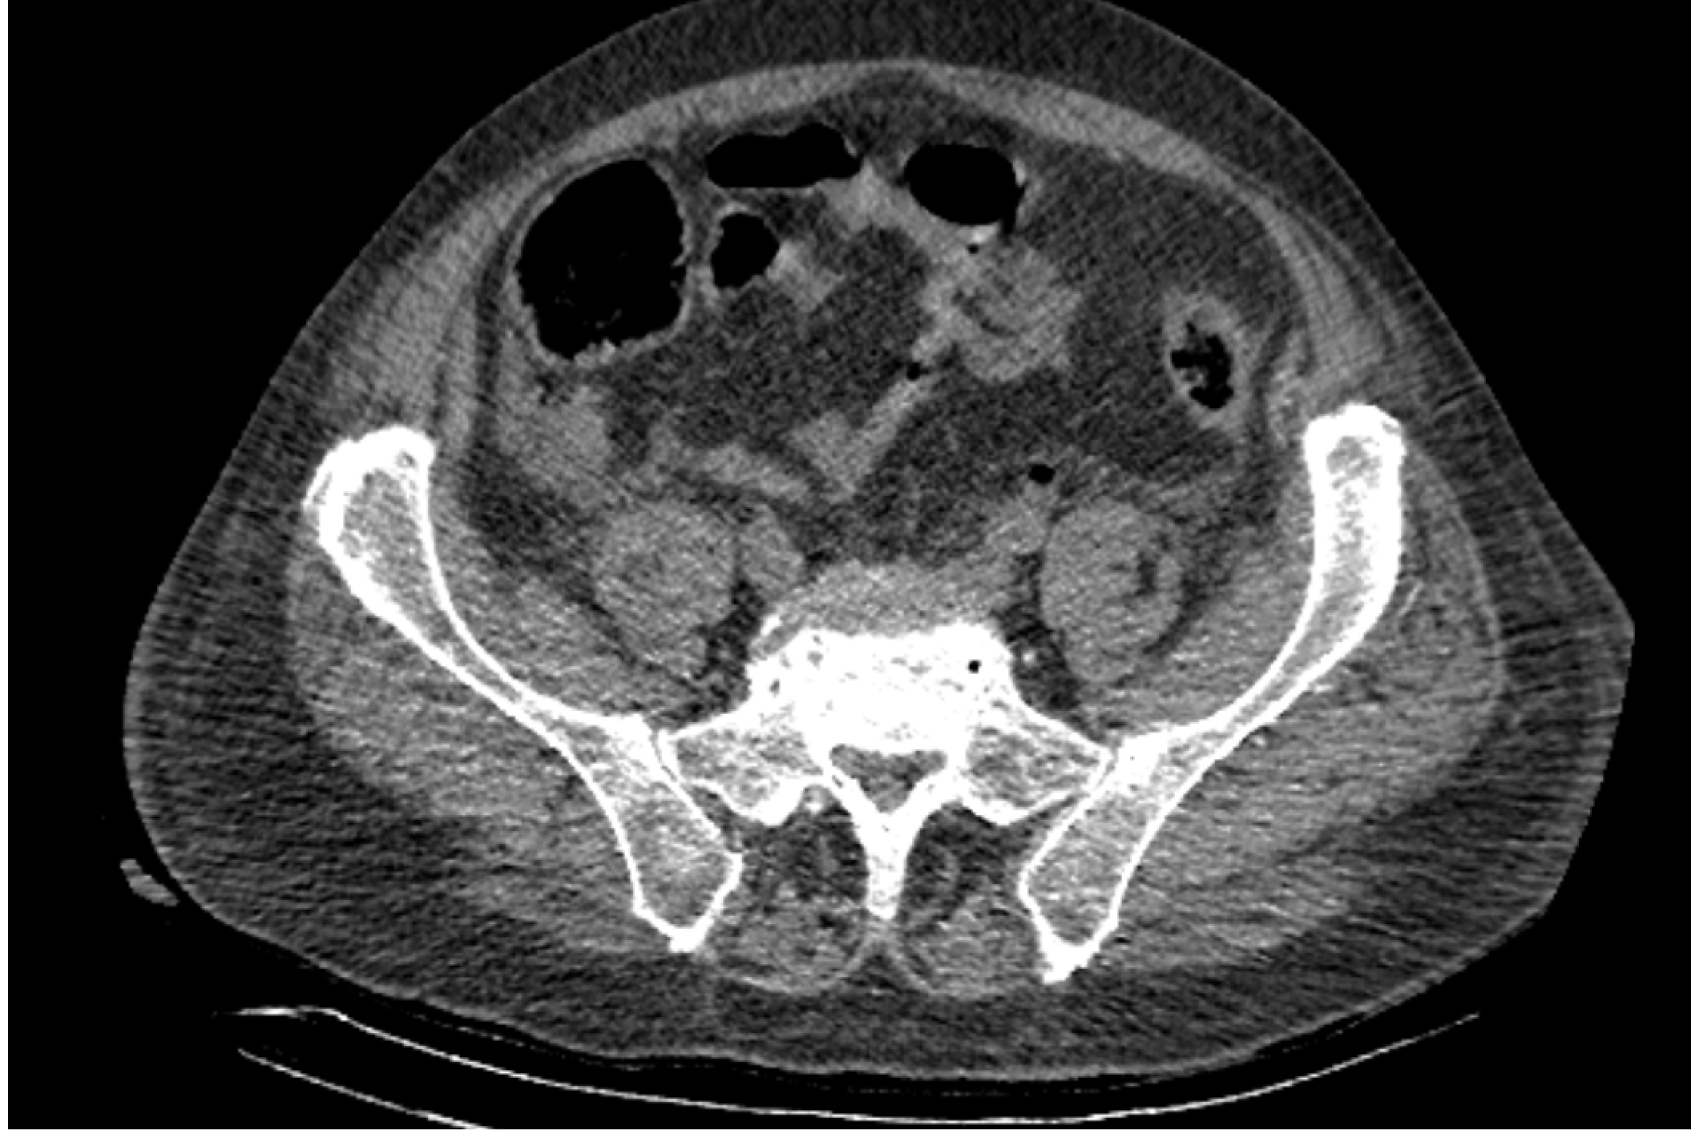

На следующий день состояние пациента оставалось тяжелым, с отрицательной динамикой, креатинин сыворотки возрос до 735,2 ммоль/л, Появились жалобы на слабость, тошноту. При осмотре: живот мягкий, вздут по всем отделам, при пальпации болезненный. Область почек не изменена, при пальпации безболезненна, патологических изменений в области почек не выявлено. Симптом поколачивания отрицательный билатерально. При УЗИ были обнаружены плевральный выпот по 300–400 мл с каждой стороны, гепатомегалия, увеличение размеров селезенки, асцит. Кроме того, в обеих почках были визуализированы тени, характерные для конкрементов. По данным компьютерной томографии (КТ) конкрементов не обнаружено, но в лоханке, на всем протяжении левого мочеточника и, частично, в правом мочеточнике, а также в мочевом пузыре визуализировался газ (рис. 1–6).

Рис. 3. Компьютерная томография органов брюшной полости, забрюшинного пространства, органов малого таза. Газ в левом мочеточнике

Рис. 4. Компьютерная томография органов брюшной полости, забрюшинного пространства, органов малого таза. Газ в почках

Рис. 5. Компьютерная томография органов брюшной полости, забрюшинного пространства, органов малого таза. Газ в левой почке

Рис. 6. Компьютерная томография органов брюшной полости, забрюшинного пространства, органов малого таза. Газ в верхнем полюсе левой почки